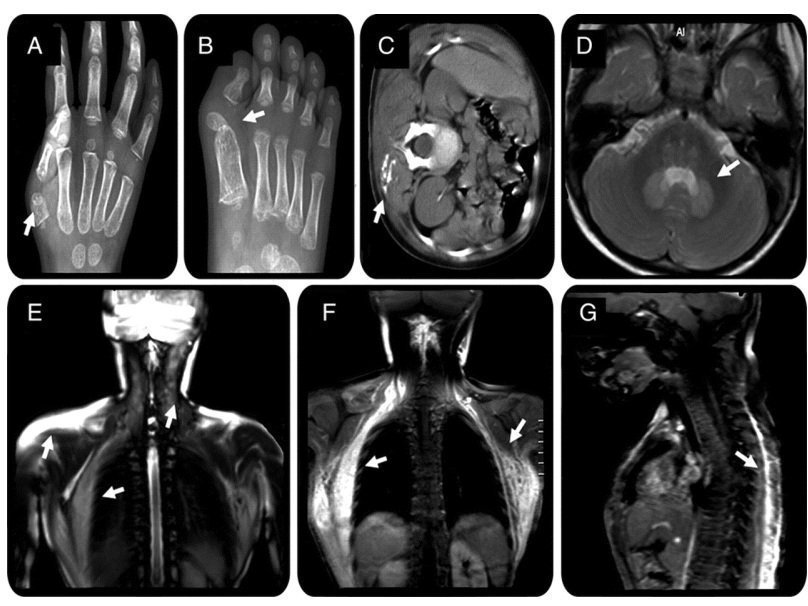

Обычный ушиб или прививка могут вызвать у носителя мутации образование опухоли, которая затем превращается в кость там, где никакой кости быть не должно. В итоге человек «костенеет», его суставы теряют подвижность, и он уже не может обходиться без посторонней помощи. Все остальные функции организма ФОП не затрагивает.

Чаще всего такую фибродисплазию на ранних стадиях развития ошибочно диагностируют как рак или фиброматоз (тип доброкачественной опухоли). Неверный диагноз и назначенное лечение (биопсия или химиотерпаия) могут усугубить развитие болезни. Удалять новые костные образования категорически нельзя – само хирургическое вмешательство может интенсифицировать окостенение и на месте удаленного непременно образуется новое.

На сайте сообщества «Живущие с ФОП» собрана основная информация о заболевании, в том числе, как его определить и подтвердить. Как правило, оно проявляется в первые годы жизни ребенка, но может оставаться незамеченным и до 15 лет. У 95% детей с ФОП наблюдается клинодактилия - искривление больших пальцев ног. При этой патологии одна или несколько фаланг пальца искривлены вовнутрь, а иногда в нем не хватает сустава. Кроме того, фибродисплазия проявляется в виде костных образований, возникших на месте травмы, шва, гематомы или просто на любом участке тела (чаще всего сначала это шея и голова). Поставить точный диагноз можно только сделав генетический тест. Сегодня в Москве это можно сделать в Медико-генетическом научном центре РАМН . Материал (кровь) можно отправить почтой, стоимость теста 6000 р.